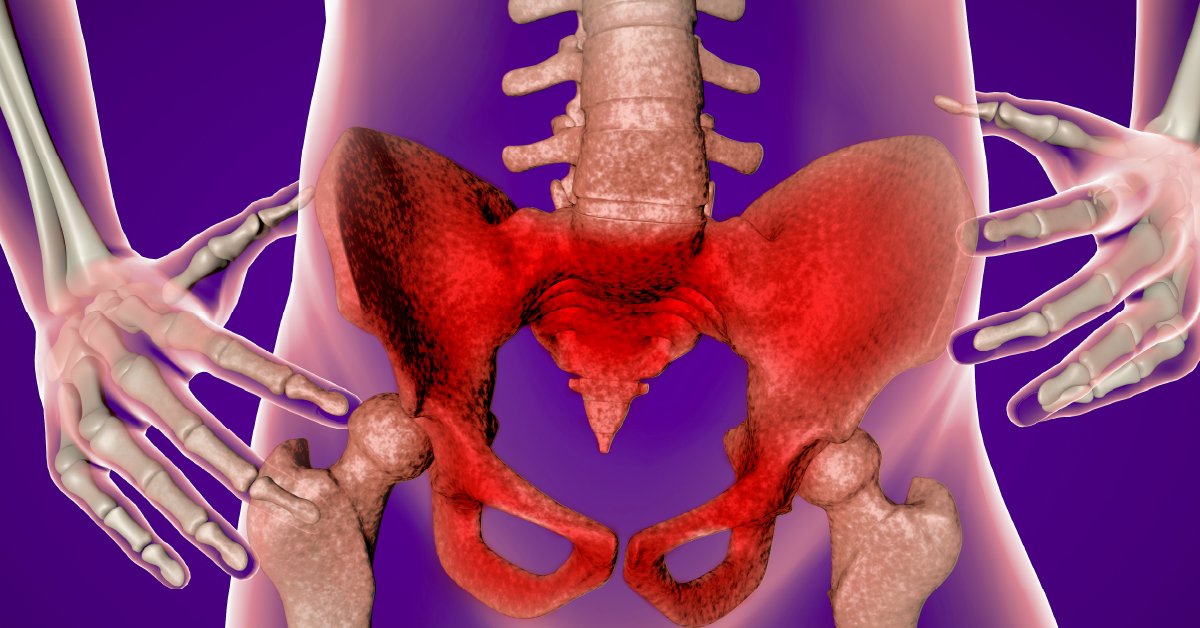

You use them to sit, stand, dance, kick, and run. Find out what makes your hips hurt, and what you can do about it. wb.md/3XqZCwA